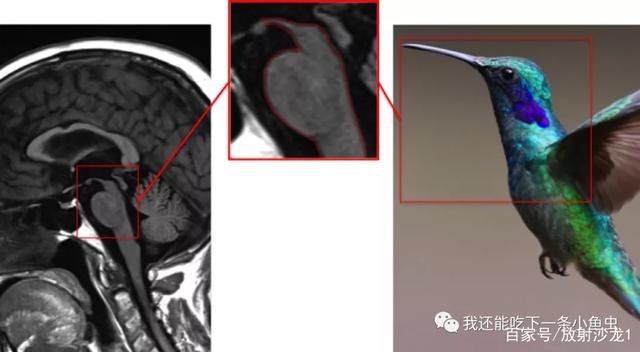

PSP是常见的非典型帕金森综合征,文献报道日本的患病率为2-17/10万,高于欧美的3.1-6.5/10万的患病率,而我国目前尚无确切的流行病学资料。PSP的发病年龄一般为50-70岁,平均病程为5-9年,特征性的临床表现为垂直性核上性眼肌麻痹伴姿势不稳易跌倒。其头部正中矢状位T1相表现为中脑萎缩和小脑上脚萎缩可以作为进行性核上性麻痹与其他帕金森综合征的鉴别诊断依据。“蜂鸟征”(图7)和“米老鼠征”(图8)(Hummingbird and Mickey Mouse Sign)的诊断特异度均达100%,诊断灵敏度分别仅68.4%和50.0%。

4610b912c8fcc3ce7ef250f9e213278ed53f20a3.jpg

图7